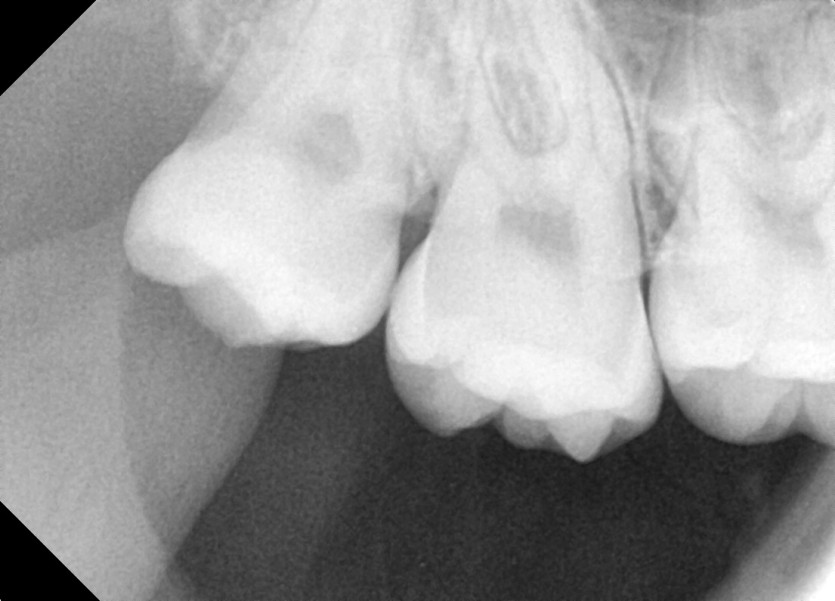

#18,48 사랑니 발치

구강 외과 전문의가 당일 발치했습니다.